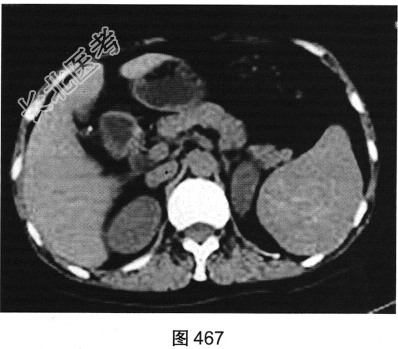

- [材料题] 患者男性,47岁,因“左上腹隐痛6个月余”就诊。腹部B超发现脾脏占位。

- 多项选择题2.[提示]患者行CT动态增强扫描,如图467~图469所示。对CT图像描述正确的是( )

A、病灶内见条索状钙化灶

B、病灶动脉期无强化

C、CT平扫呈不均匀稍低密度

D、左肾被病灶侵犯

E、病灶门脉期显著强化

F、病灶边界清晰,具有包膜